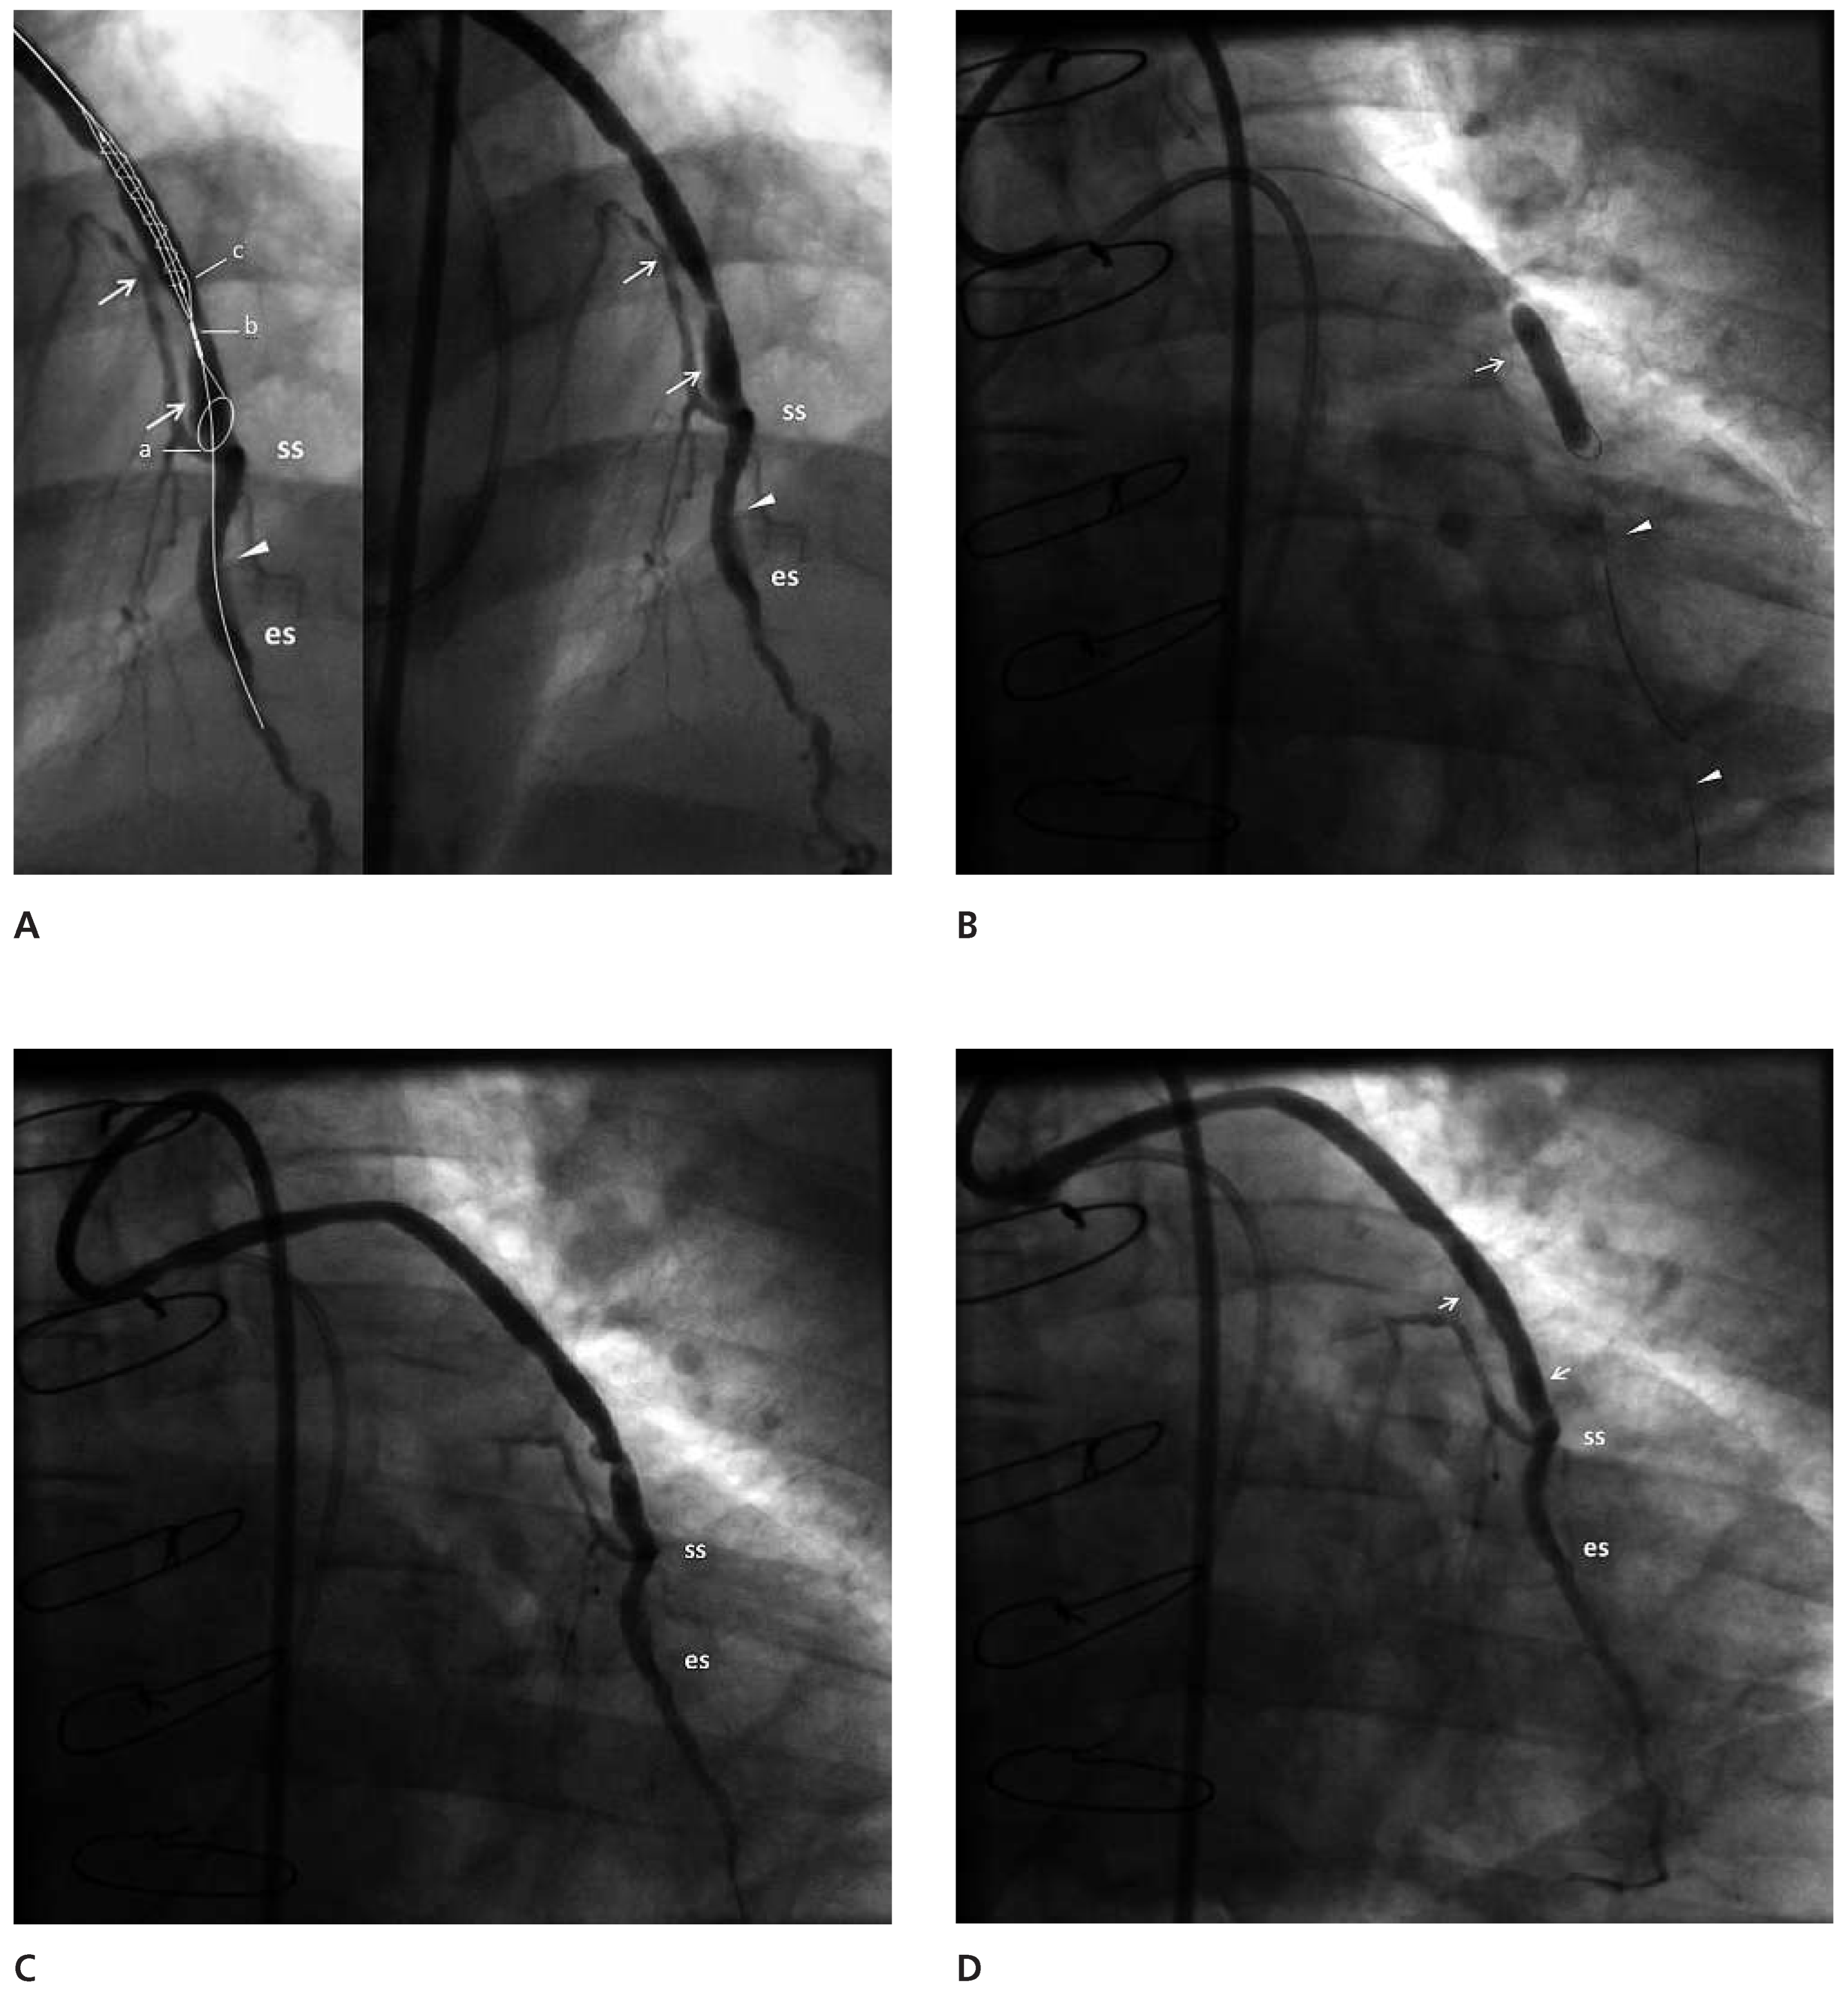

Angioplasty of the distal segment of the LAD followed by angioplasty of the vein graft was performed with a JR4 8F guiding catheter. The angioplasty of the distal LAD was performed successfully and then a FilterWire™ 3.5–5.5 (FilterWire™ EZ System, Boston Scientific Corp) was deployed parallel to the guidewire that extended to the distal LAD, with the FilterWire™ loop proximal to the first of the distal anastomoses. A Sprinter 4/20 balloon (Medtronic, Inc.) was advanced on the guidewire, with its distal tip close to the FilterWire™ loop, closer than it would have been possible if it had been advanced on the FilterWire™ itself (Figure 1B). It was inflated to 18 atm with the intention to disrupt the plaque and get the maximum amount of debris collected during the “protection” phase. The FilterWire™ was properly closed and removed with the guidewire remaining in place. The vein graft plaque was obviously disrupted but the flow remained good (Figure 1C). In the filter there were two solid whitish pieces of the vein graft wall, one large and one small. (Figure 2). A stent Endeavor® Resolute 4/18 (Medronic, Inc.) with a stent balloon/reference artery diameter ratio 1:1, was advanced over the guidewire and deployed at the site of the disrupted plaque at 10 atm. Despite the presence of a small (10–20%) compression of the stent, no further dilatation was performed (Figure 1D). The flow to the LAD through the graft was good with no evidence of branch occlusion or diminished flow.

Figure 2. The FilterWire™ and the atheromatous material that was captured. The arrow points to the balloon stop.